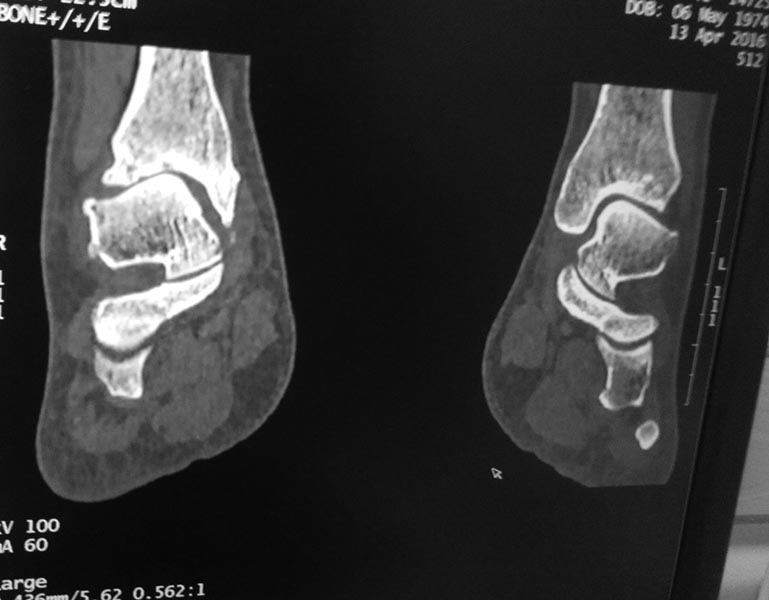

Интересный случай. А рентген сделан под нагрузкой? Не похоже. Обязательно нужно под нагрузкой сделать. И обещанной КТ что-то не видно. Артроз тут, конечно, есть. Хотя далеко не крайняя степень. Думать об артродезе вроде рановато. Но и какого рада корригирующая остеотомия могла бы помочь тоже по этим снимкам не скажешь.

Я бы еще повниматьнее к таранной кости присмотрелся. Не было ли перелома ее шейки? На КТ срез подозрительный, но только один.

Желательно все-таки точно убедиться в наличии перелома таранной кости. Если он не сросся за 3 года, то ситуация становится еще более непонятной. Ждем снимков под нагрузкой и дополнительных срезов КТ.

Вколоченный перелом шейки таранной шейки кости,переднего края Б/берцовой кости.МОС шейки таранной кости,удаление костно-хрящевых экзостозов.